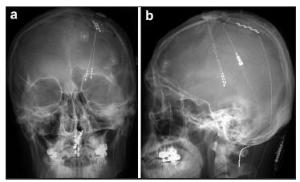

20170512094150 Figure 2 Anterior-posterior a and lateral b projections of skull x-ray films of a patient (#10) who underwent a simultaneous DBS/ MCS trial for intractable, chronic neuropathic pain. This patient had both thalamic Vc and internal capsule DBS electrodes combined with a left-side MCS electrode. Note the previously implanted C1–C2 paddle lead for treatment-resistant complex regional pain syndrome with whole-body involvement, which was more severe in the right hemibody. In this particular patient, we obtained >50% pain relief with the initial MCS trial. However, thalamic Vc stimulation aggravated the hemibody pain. The prominent analgesic effect of MCS faded postoperatively within six months. However, the patient still today (24 months after MCS) uses chronic MCS for unremitting pain. He judged MCS as being much more effective than spinal cord stimulation.